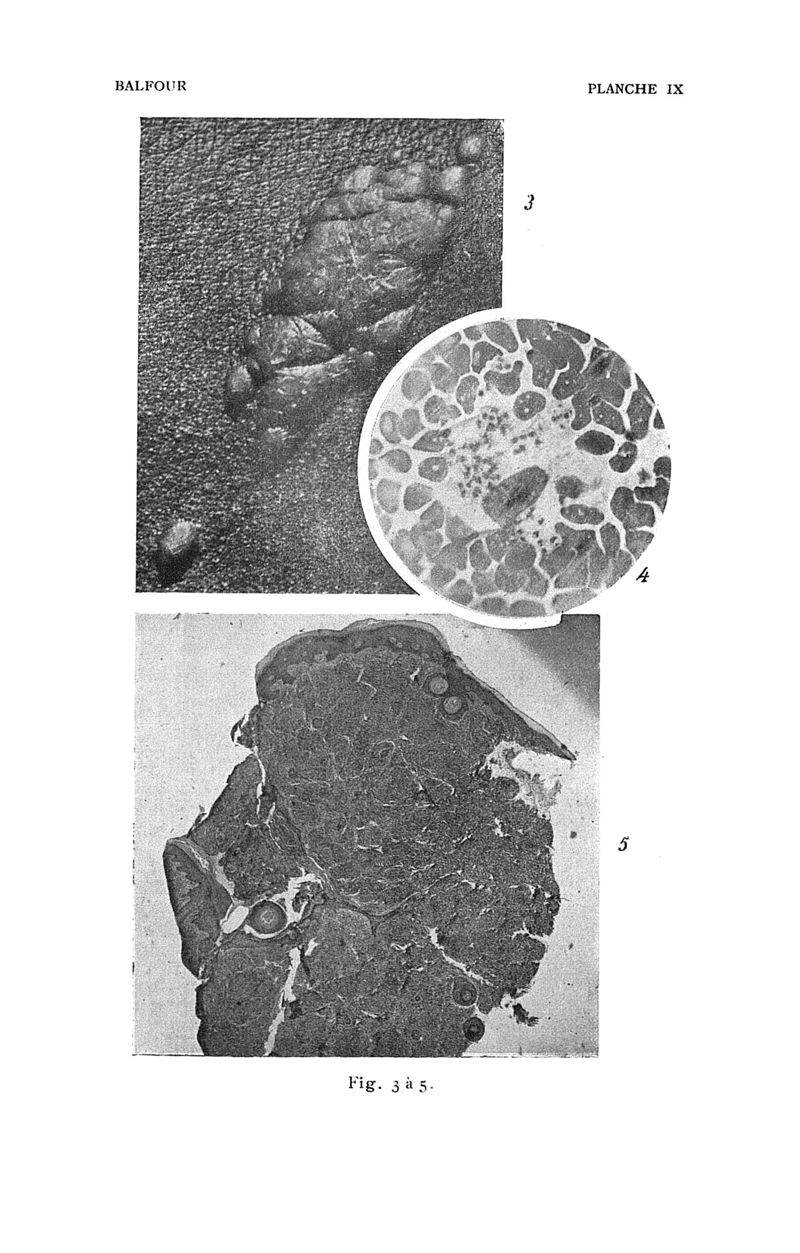

Bulletin de la Société de pathologie exotique

1909, tome 02. - Paris : Masson, 1909.